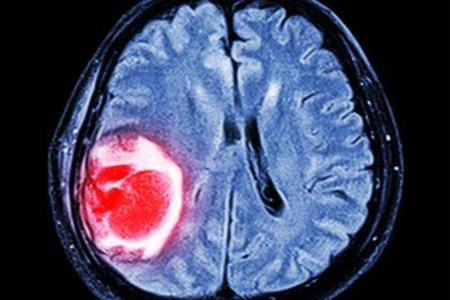

腦瘤是一種發生在大腦内部的腫瘤,它可能是良性的,也可能是惡性的。無論腦瘤的類型如何,它都是一種嚴重的神經系統疾病,可能會對患者的生命健康産生重大影響。

腦瘤是指發生在大腦内部的腫瘤,它可以發生在大腦的任何部位。根據其性質,腦瘤可以分爲良性和惡性兩種。良性腦瘤生長緩慢,邊界清晰,通常不會擴散到其他部位;而惡性腦瘤則生長迅速,邊界不清,容易擴散和轉移。此外,腦瘤還可能分爲顱内腦瘤和顱外腦瘤兩種,其中顱内腦瘤是指發生在大腦内部的腫瘤,而顱外腦瘤則是指發生在大腦外部的腫瘤。

診斷腦瘤需要進行一系列的檢查,包括頭顱CT、MRI、PET-CT等影像學檢查,以及血液檢查、神經心理學檢查等。通過這些檢查,醫生可以确定腦瘤的位置、大小、性質以及與周圍組織的 關系,從而制定出合适的治療方案。